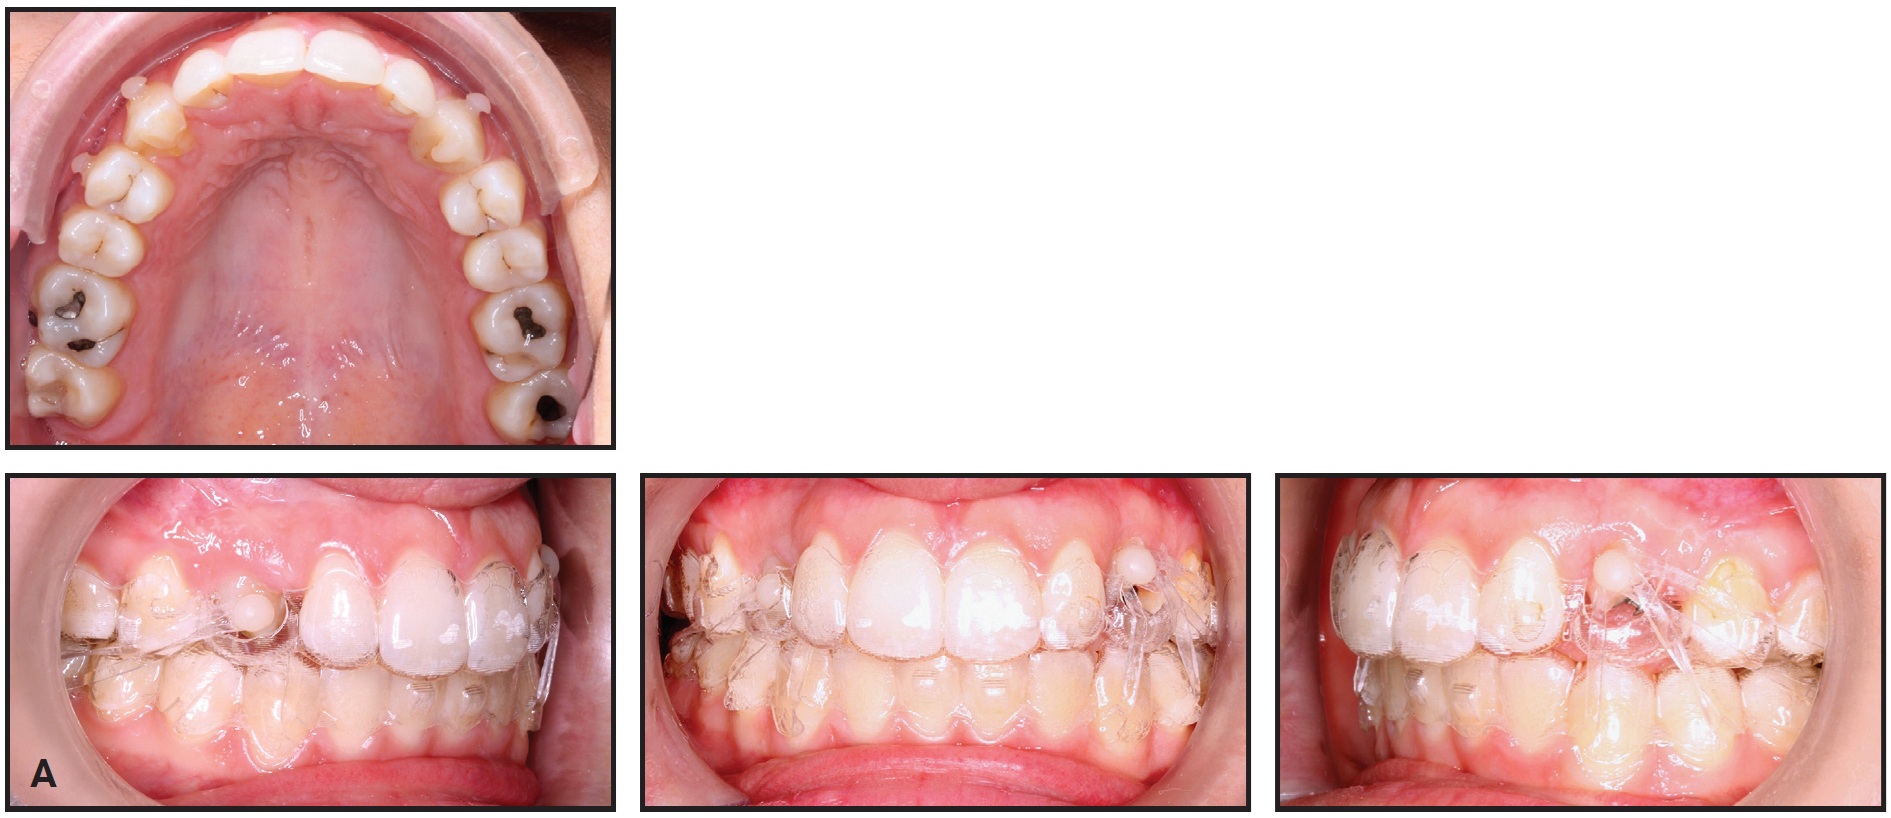

The treatment plan was divided into two stages (see box). The first, involving arch expansion and space preparation for the canine, would require 44 sets of aligners, changed weekly. In the second stage, which would involve 32 sets of aligners changed every two weeks, the canine would be exposed, and traction would be performed.

The first set of aligners was designed to expand the maxillary arch and prepare space for the upper premolars with sequential molar distalization (Fig. 8). Class II elastics (3⁄16", 4.5oz) were worn from the first premolars to the lower molars to prevent labial movement of the premolars. Next, the premolars were derotated and moved buccally into the arch. Using the contralateral canine’s mesiodistal width as a guide, about 7.5mm of space was prepared for the impacted canine.

Fig. 8 Case 2. ClinCheck plan of first treatment stage, involving expansion of maxillary arch and preparation of space for impacted canine.

After two months, the canine was surgically exposed. A button was bonded to the labial side of the upper right first molar, and elastic thread was used to apply a distobuccal force vector, with the primary objective of moving the canine away from the incisor roots.

After the first stage of treatment, the canine was partially visible and had moved buccally into the arch. Because 30° of derotation would be required for alignment, in addition to extrusion and buccal root-torquing movements, a lingual fixed appliance would be used as an auxiliary; the ClinCheck* plan was modified accordingly (Fig. 9). Lingual .022" Victory** lower-incisor twin brackets were bonded from the upper right central incisor to the second premolar, and an .016" nickel titanium lingual archwire was engaged to correct the rotation. At the same time, clear aligners were used to extrude the upper right canine, with elastics (3⁄16", 3.5oz) worn from the canine hook to cutouts on the labial sides of the canine and first premolar.

Fig. 9 Case 2. A. ClinCheck plan of first refinement stage, showing modifications to account for use of sectional fixed appliance on lingual side of upper right segment. B. Fixed lingual appliance used as auxiliary during first refinement stage.

Four months later, buccal root torque was applied to the canine with an .016" × .022" rectangular TMA*** lingual archwire. During the detailing phase, the fixed lingual appliance was removed, and treatment continued with 12 sets of clear aligners, changed weekly. To reduce the visibility of the attachments, they were placed on the lingual sides of all upper anterior teeth except the right canine.

After 30 months of active treatment, the maxillary and mandibular arches were well aligned, the posterior crossbite was corrected, the overjet and overbite were within normal ranges, and bilateral Class I canine and molar relationships were obtained (Fig. 10). At the end of treatment, a gingivectomy of the canine was performed to align its soft-tissue contours with those of the adjacent teeth.